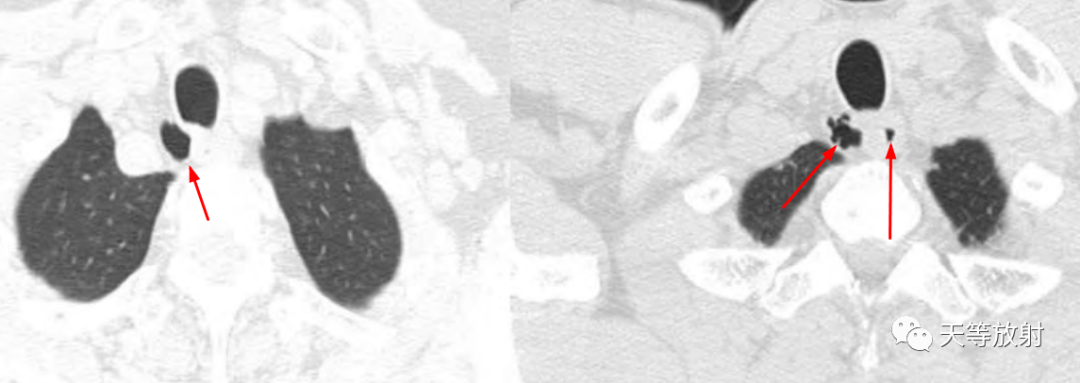

冠状位及矢状位观察,囊影位于胸廓入口右侧旁。

文献病例:气管旁憩室,细线样密度影与气管相连通。

上图,气管憩室,有一较短细的管道相通,类似小蝌蚪样改变。